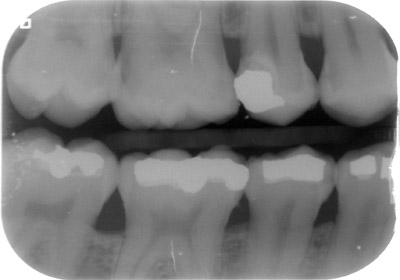

• la realització de dos radiografies intraorals (aletes de mossegada) o extraoral (ortopantomografia ) per arribar al diagnóstic més acurat.

A més, és molt important la realització de radiografies de dignòstic, tant a la primera visita com a les futures revisions, ja que el major nombre de les càries comencen als punts de contacte entre les dents o queixals, i aquests són innaccesibles visualment amb una exploració convencional.

aletadreta aletaesq   ortopanto